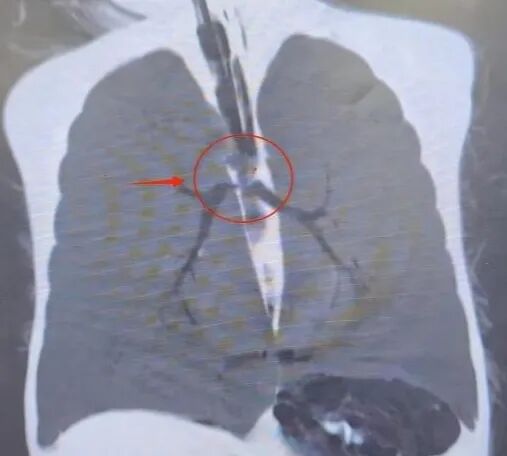

为明确诊断,急诊科立即开启绿色通道,全程护送患儿完成紧急胸部CT检查。检查结果很快就出来了:气管隆突上方卡有异物。这正是导致患儿呼吸困难、意识丧失的“元凶”!明确诊断后,耳鼻咽喉头颈外科、急诊科、重症医学科和手术室迅速完善术前各项准备,患儿被以最快速度推入手术室。此时的宝宝已陷入深度昏迷,手术床上微弱的呻吟声,每一声都牵动着在场每一位医护人员的心。